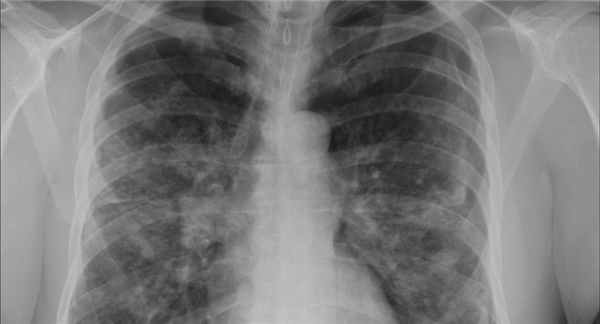

Стадии саркоидоза определяют по данным обзорной рентгенографии грудной клетки.

Стадия I: двустороннее увеличение бронхолегочных лимфоузлов

Стадия II: двустороннее увеличение бронхолегочных лимфоузлов и диффузное поражение легочной паренхимы, сетчатая перестройка легочного рисунка, но иногда множественные очаговые или милиарные тени

Стадия III: поражение легочной паренхимы без увеличения бронхолегочных лимфоузлов

Вероятность спонтанной ремиссии (самостоятельного выздоровления) при стадиях I, II и III составляет 80, 50 и 30% соответственно.

В зависимости от изменений на рентгенограмме органов грудной клетки выделяют 3 стадии саркоидоза легких:

- I – увеличены внутригрудные лимфатические узлы;

- II – патологический процесс двусторонний, определяется инфильтрация ткани легких в сочетании с поражением внутригрудных лимфатических узлов;

- III – выраженный фиброз ткани легких; внутригрудные лимфатические узлы не увеличены; пневмофиброз постепенно разрастается, его очаги создают сливные конгломераты.